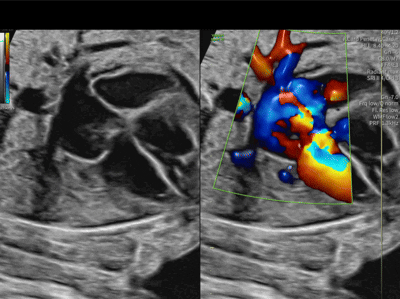

Cor triatriatum sinister

Is this Systemic or Venous return

What is Pulmonary Venous return to the LA